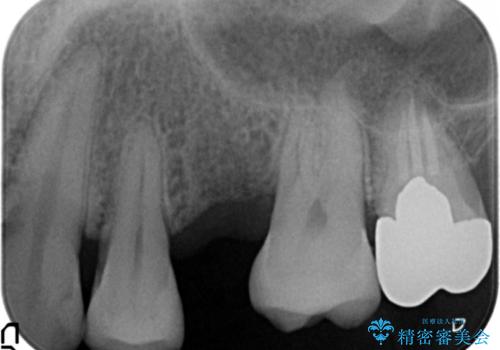

「違和感もなく、まるで自分の歯のようにしっかり咬めます!」と大変喜んで頂けました。

インプラントの種類:ストローマン BLT

被せ物の種類:オールセラミッククラウン スタンダード